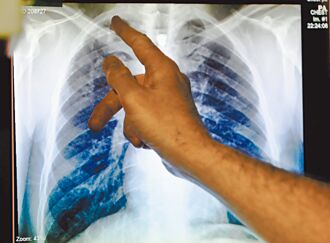

WHO:結核病 頭號傳染病殺手

世界衛生組織(WHO)29日指出,2023年全球結核病新增病例達到歷史新高820萬例,較2022年的750萬成長顯著。結核病取代新冠病毒,再度成為全球頭號傳染病殺手,一年內死亡人數幾乎達到愛滋病的兩倍之多。疾管署副署長羅一鈞分析,新冠期間因為封城措施,導致追蹤病患沒有辦法獲得妥善的治療和追蹤,也無法支持結核病的篩檢,是全球失控原因,所幸台未出現這個問題。

WHO警告!結核病接棒新冠 成全球首要傳染病死因

根據世界衛生組織(WHO)發布報告,結核病在2023年取代COVID-19成為傳染性疾病相關死亡案例中的首要原因。疾管署副署長羅一鈞分析,可能與新冠疫情期間國際封城,造成衛生體系崩壞,導致追蹤病人無法獲得治療、篩檢率大幅下降,才導致全球失控。不過台灣疫情期間,未曾經歷此特殊現象,仍會持續擴大找出潛伏感染者,目標讓我國結核病發生率,由2005年的每十萬人口73人逐年下降至2023年的每十萬人口28人。